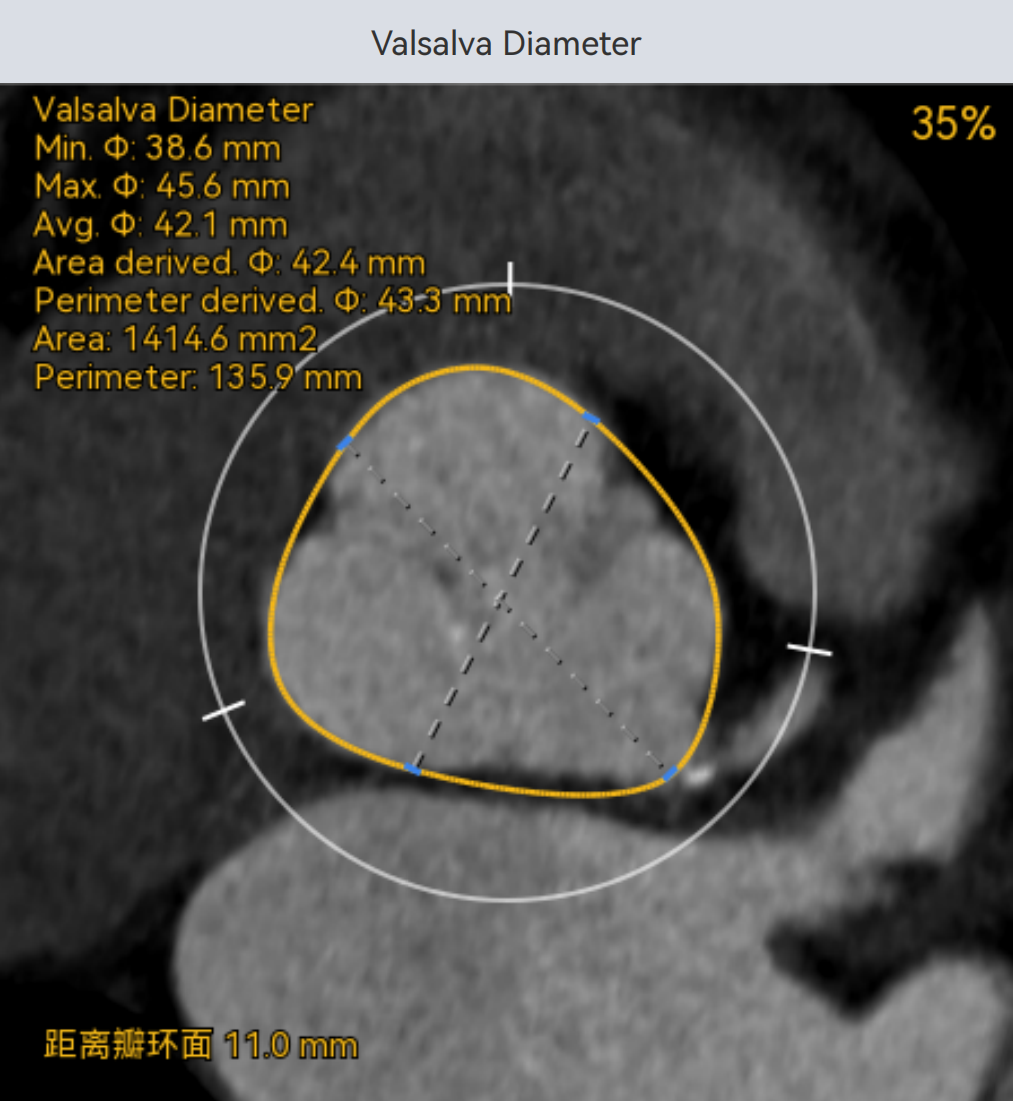

三叶式主动脉瓣,瓣叶增厚,瓣环周长76mm,选用S号TaurusTrio瓣膜。